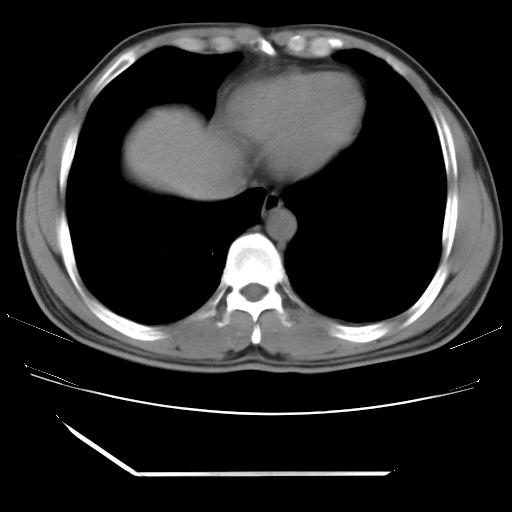

左肺舌叶病变。主体病灶呈类圆形中心密度低,成液化趋势周边班片影分布

考虑肺脓肿

虽然实验室检查支持炎性病变,且病变内有坏死改变(中央呈大片状低密度影),但仍不能掉以轻心,鳞癌也可以有这种影像改变。